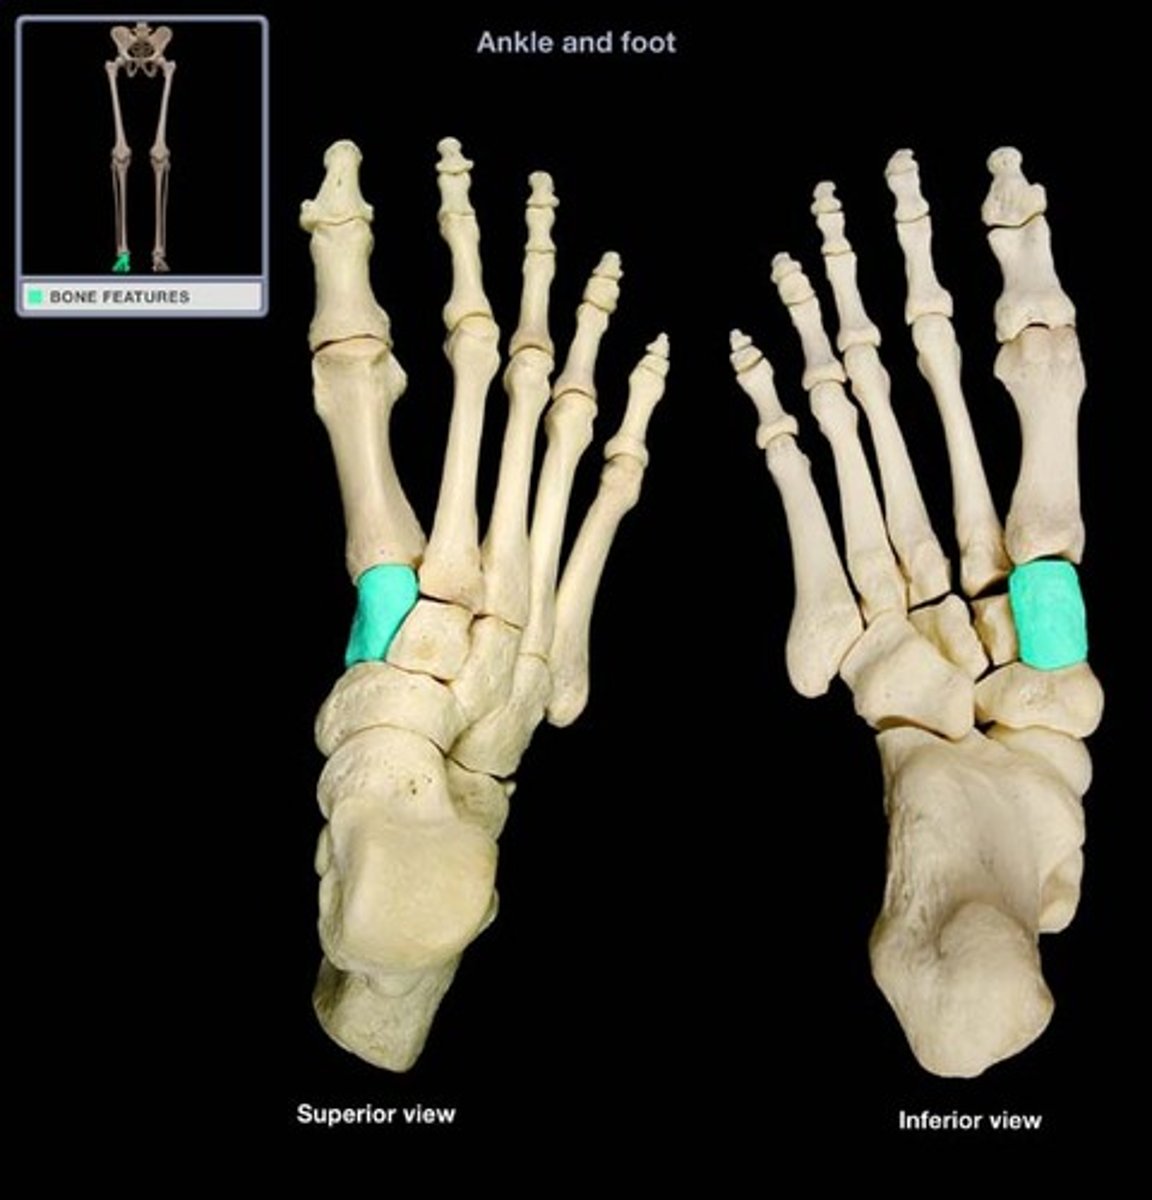

Cuboid bone